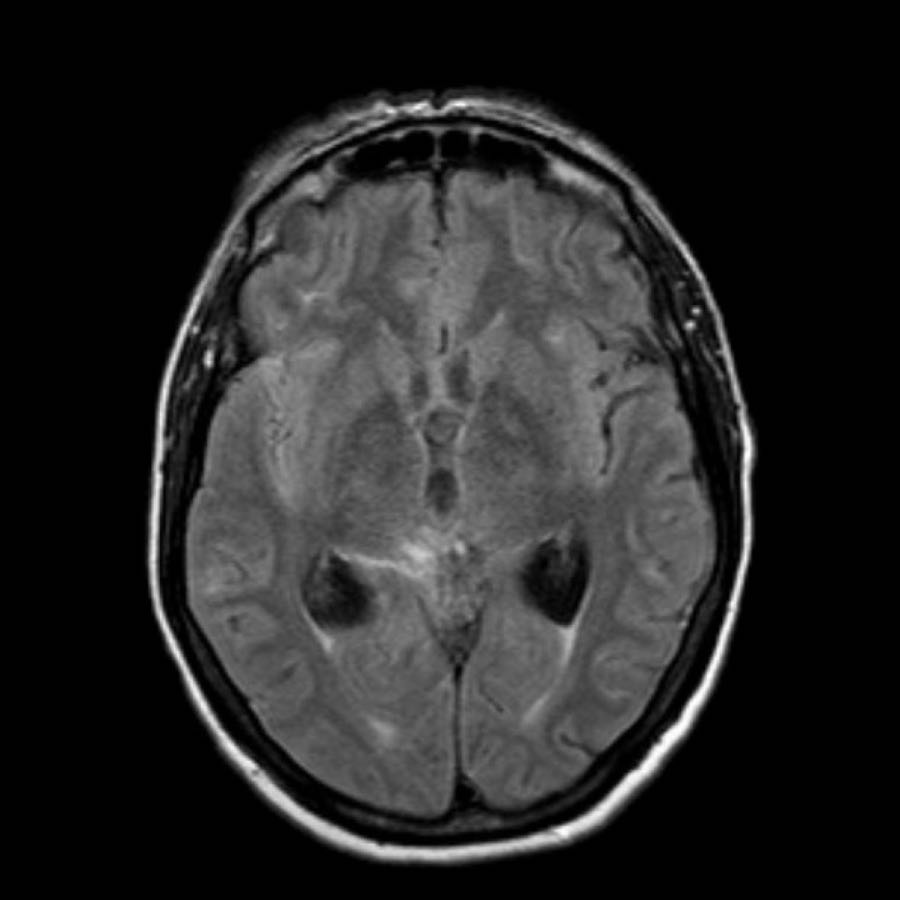

Những hình ảnh này thuộc về một bệnh nhân nghi ngờ SAH xảy ra vài ngày trước.

NECT và hầu hết các chuỗi xung MRI đều bình thường.

Tiếp tục với các hình ảnh FLAIR…

Hình ảnh FLAIR cho thấy tín hiệu tăng cao trong khoang dưới nhện.

Các mũi tên chỉ bể gian cuống não ở phía trước và bể vòng (ambient cistern) ở phía sau.